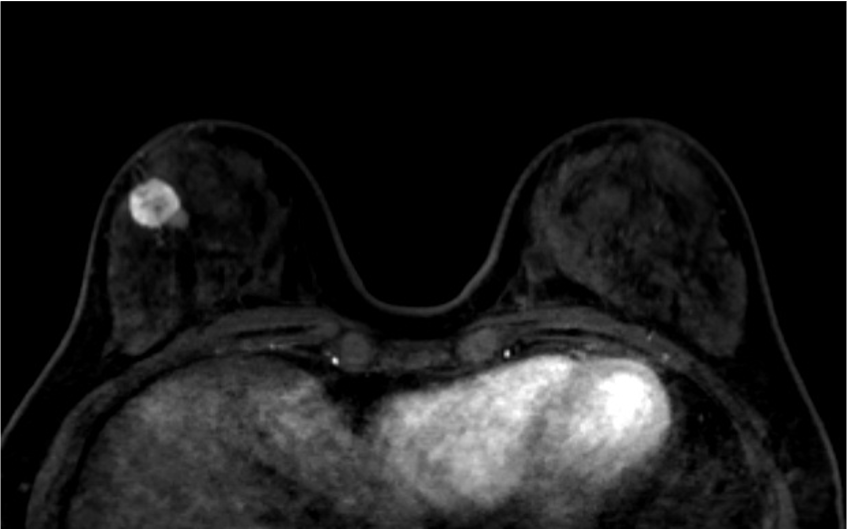

4. ダイナミックMRI (造影前 早期相 遅延相)

早期相で、乳腺の辺縁にBPE(矢印)を認めるが、その範囲は広くなくmildと判定する。乳癌の病変は、早期相から急速に造影され、遅延相でwash outがみられる。BPEは、遅延相で拡大し増強している。